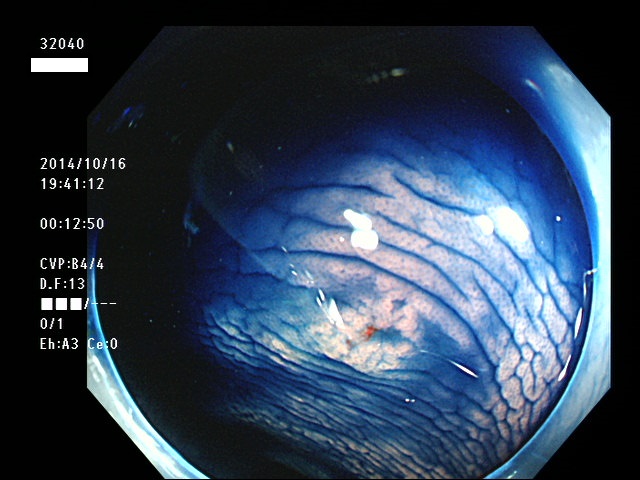

上記100名より抽出した平坦・陥凹型腺腫(=癌化の危険が高いが見落としやすい病変)の内視鏡写真